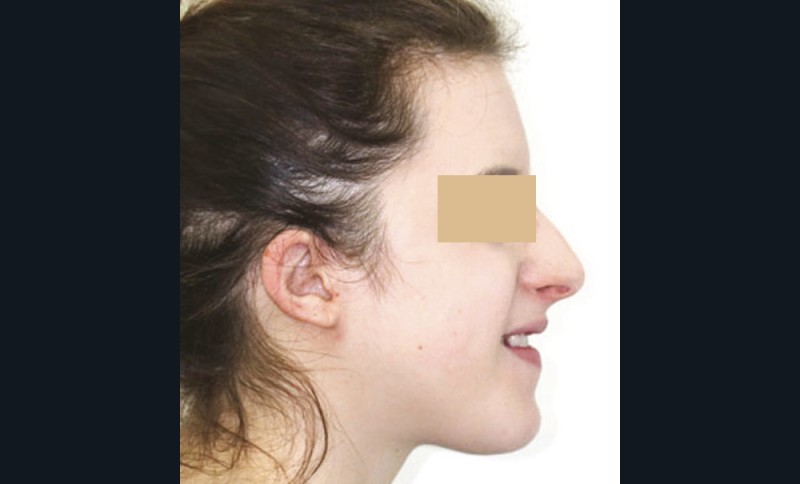

La patiente, âgée de 24 ans, en bonne santé générale, consulte en orthodontie pour raisons esthétiques. Elle présente une classe III squelettique par rétrognathie maxillaire sur un schéma facial hyperdivergent (fig. 1a-b).